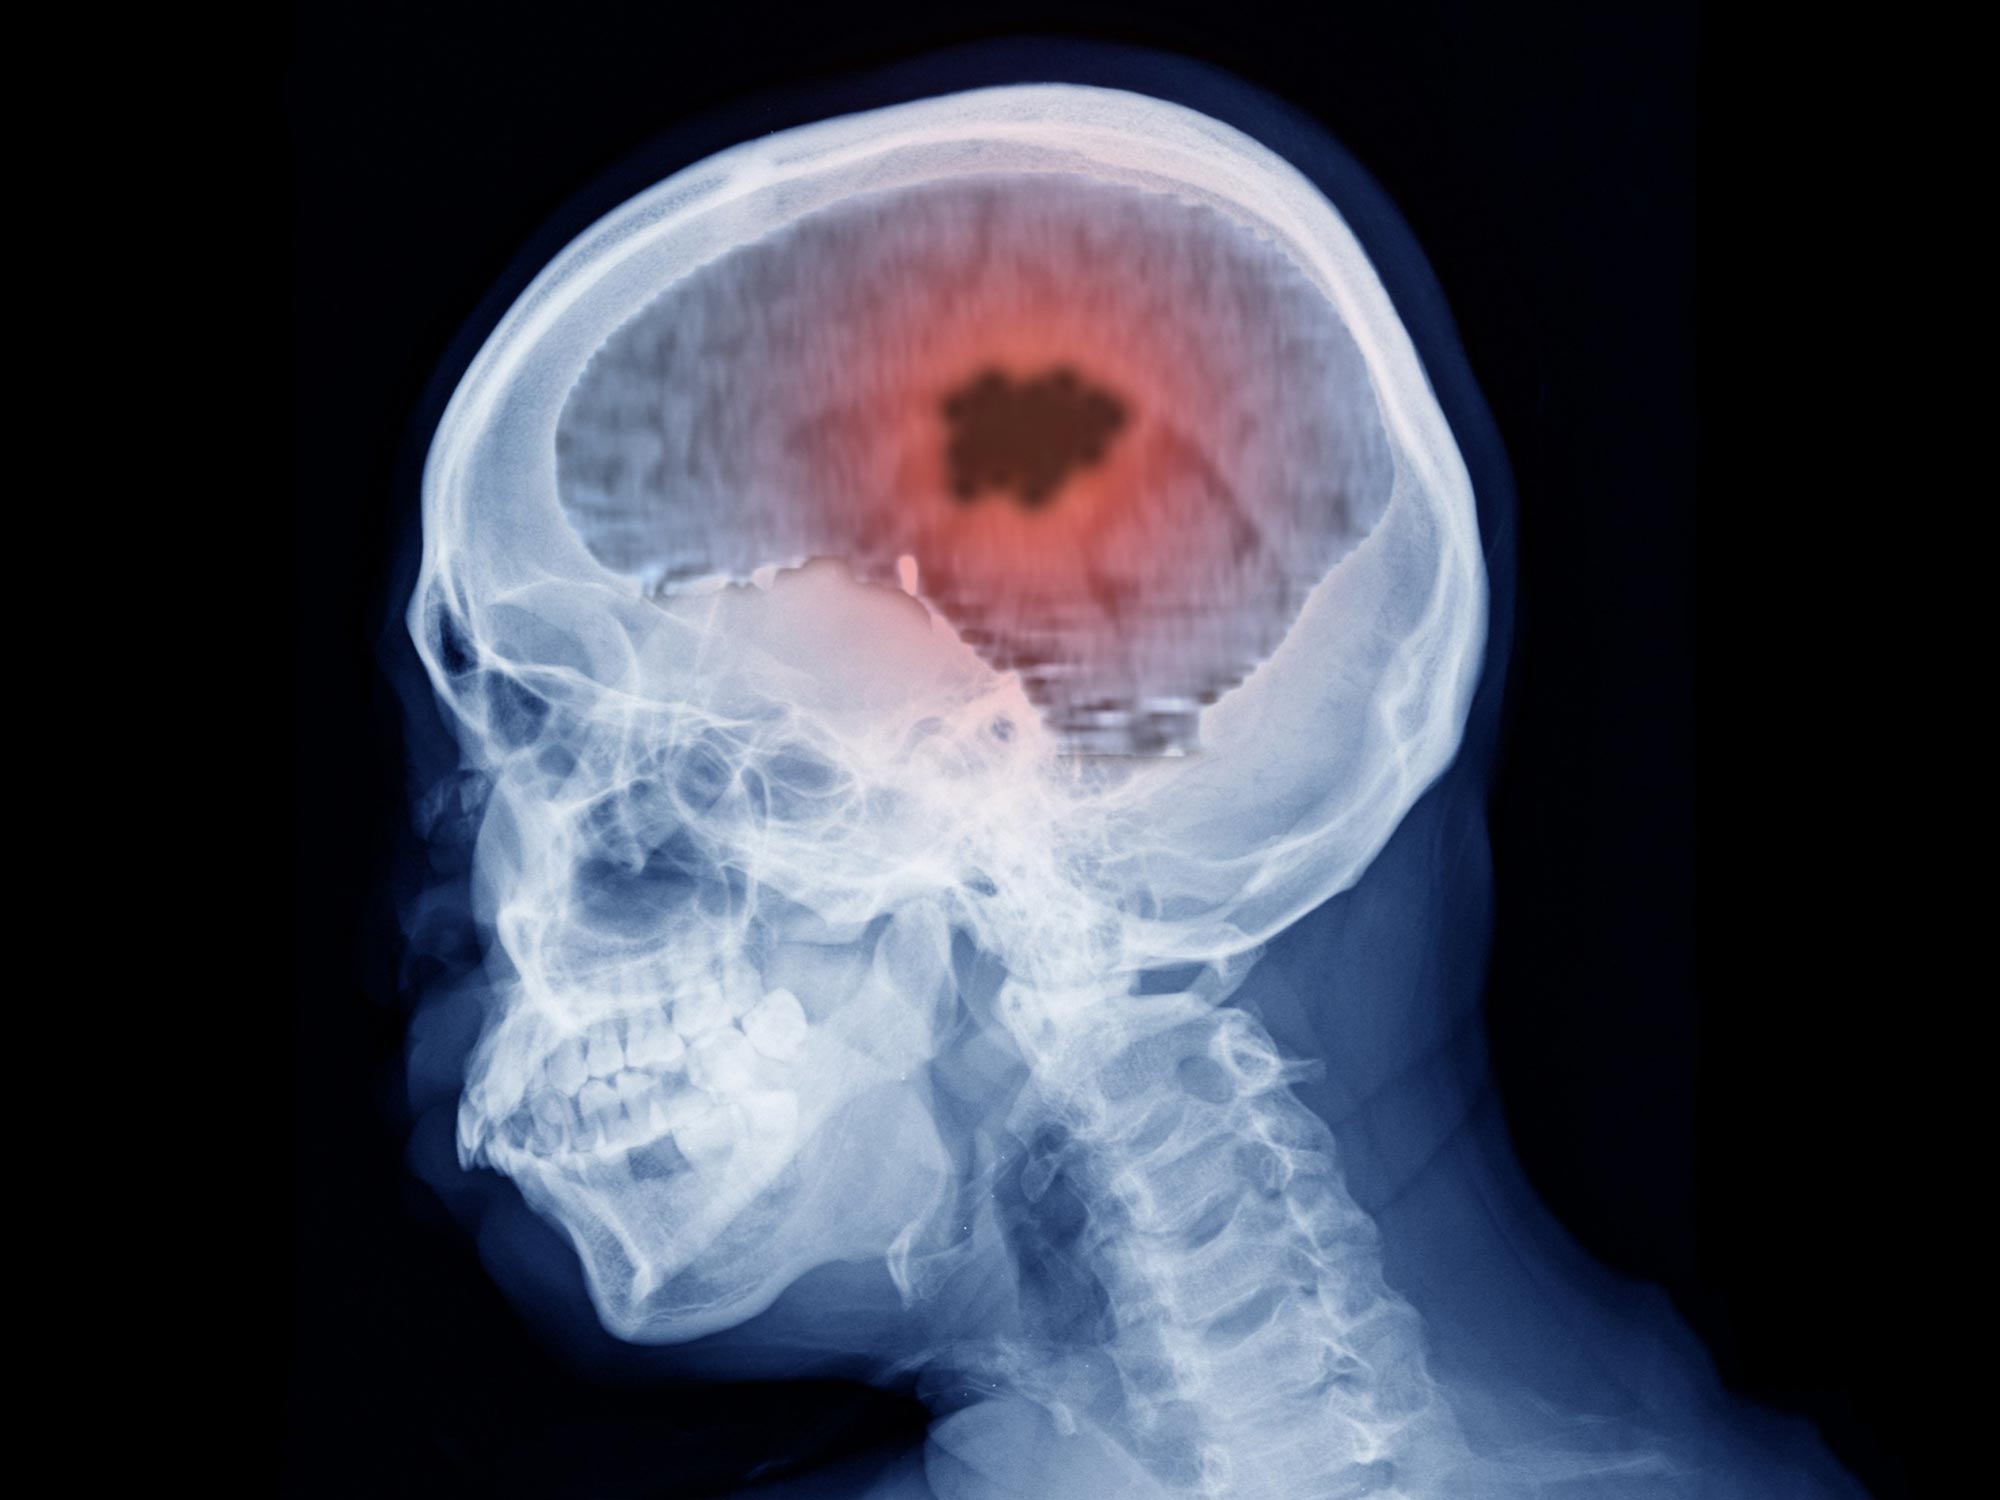

Can One X Ray Cause Cancer . The low doses of radiation used for imaging tests might increase a person’s cancer risk. Patients want to know if radiation from mammograms, bone density tests, computed tomography (ct) scans, and so forth will increase their risk of developing cancer. Learn what we know about these types of. The evidence they can cause cancer comes from many. There's always questions about radiation exposure from medical imaging. In large doses, radiation can cause serious tissue damage and increase a person’s risk of later developing cancer.

The low doses of radiation used for imaging tests might increase a person’s cancer risk. There's always questions about radiation exposure from medical imaging. The evidence they can cause cancer comes from many. In large doses, radiation can cause serious tissue damage and increase a person’s risk of later developing cancer. Learn what we know about these types of. Patients want to know if radiation from mammograms, bone density tests, computed tomography (ct) scans, and so forth will increase their risk of developing cancer.